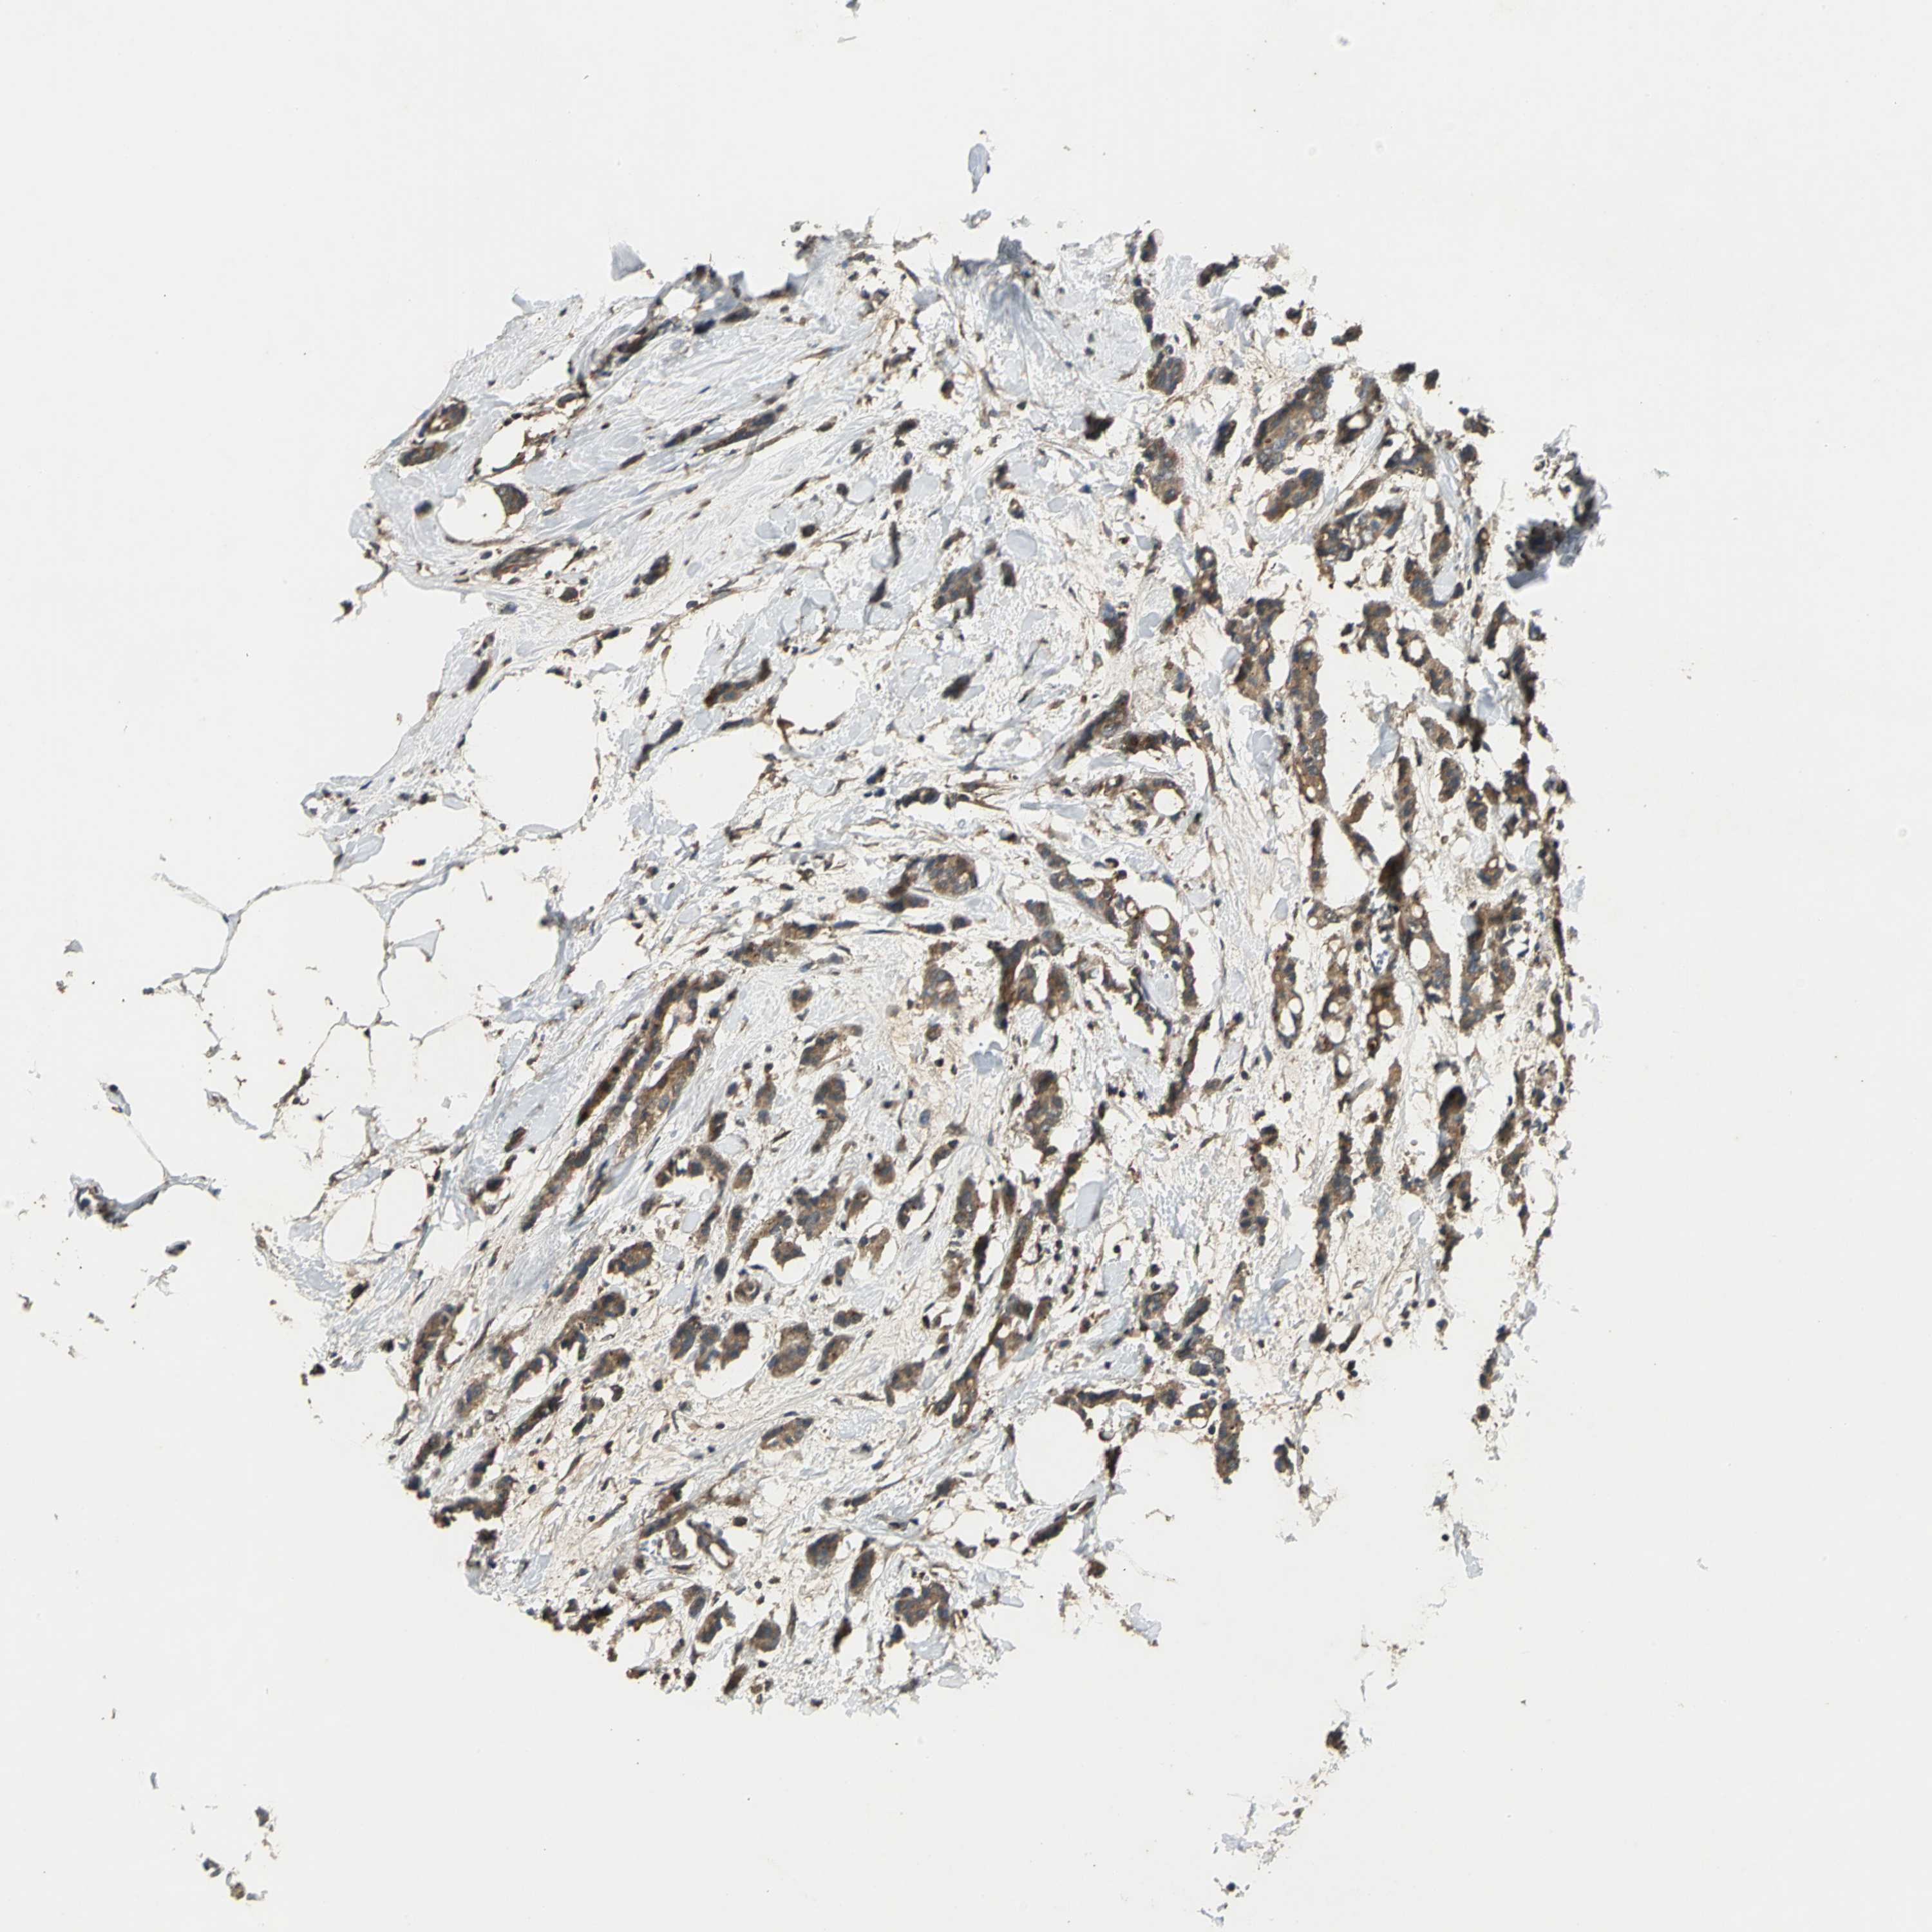

CANCER BREAST CANCER Show tissue menu

BRCA TCGA BRCA VALIDATION PROTEIN EXPRESSION

Breast cancer

Human cancer